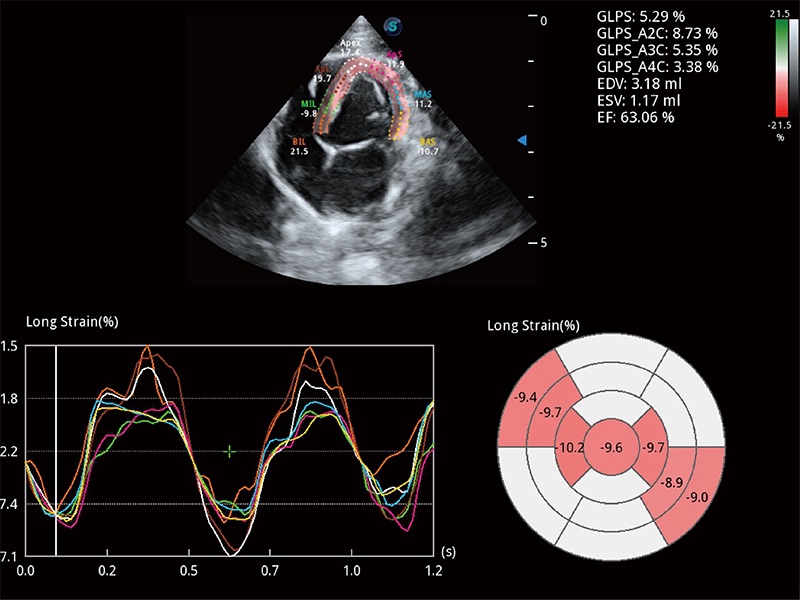

通过心肌识别技术与二维斑点追踪技术相结合,对心脏的超声图像进行量化分析。计算心肌17个节段的应变、应变率、速度、位移等,并通过牛眼图的形式进行呈现。

具备多种协议可选,同时支持17阶段划分法和专业的SE报告。

能够基于左心室壁追踪和辛普森法,自动计算射血分数,支持多个可移动点描迹,与手动测量相比,极大节省了动物医生的时间和精力。